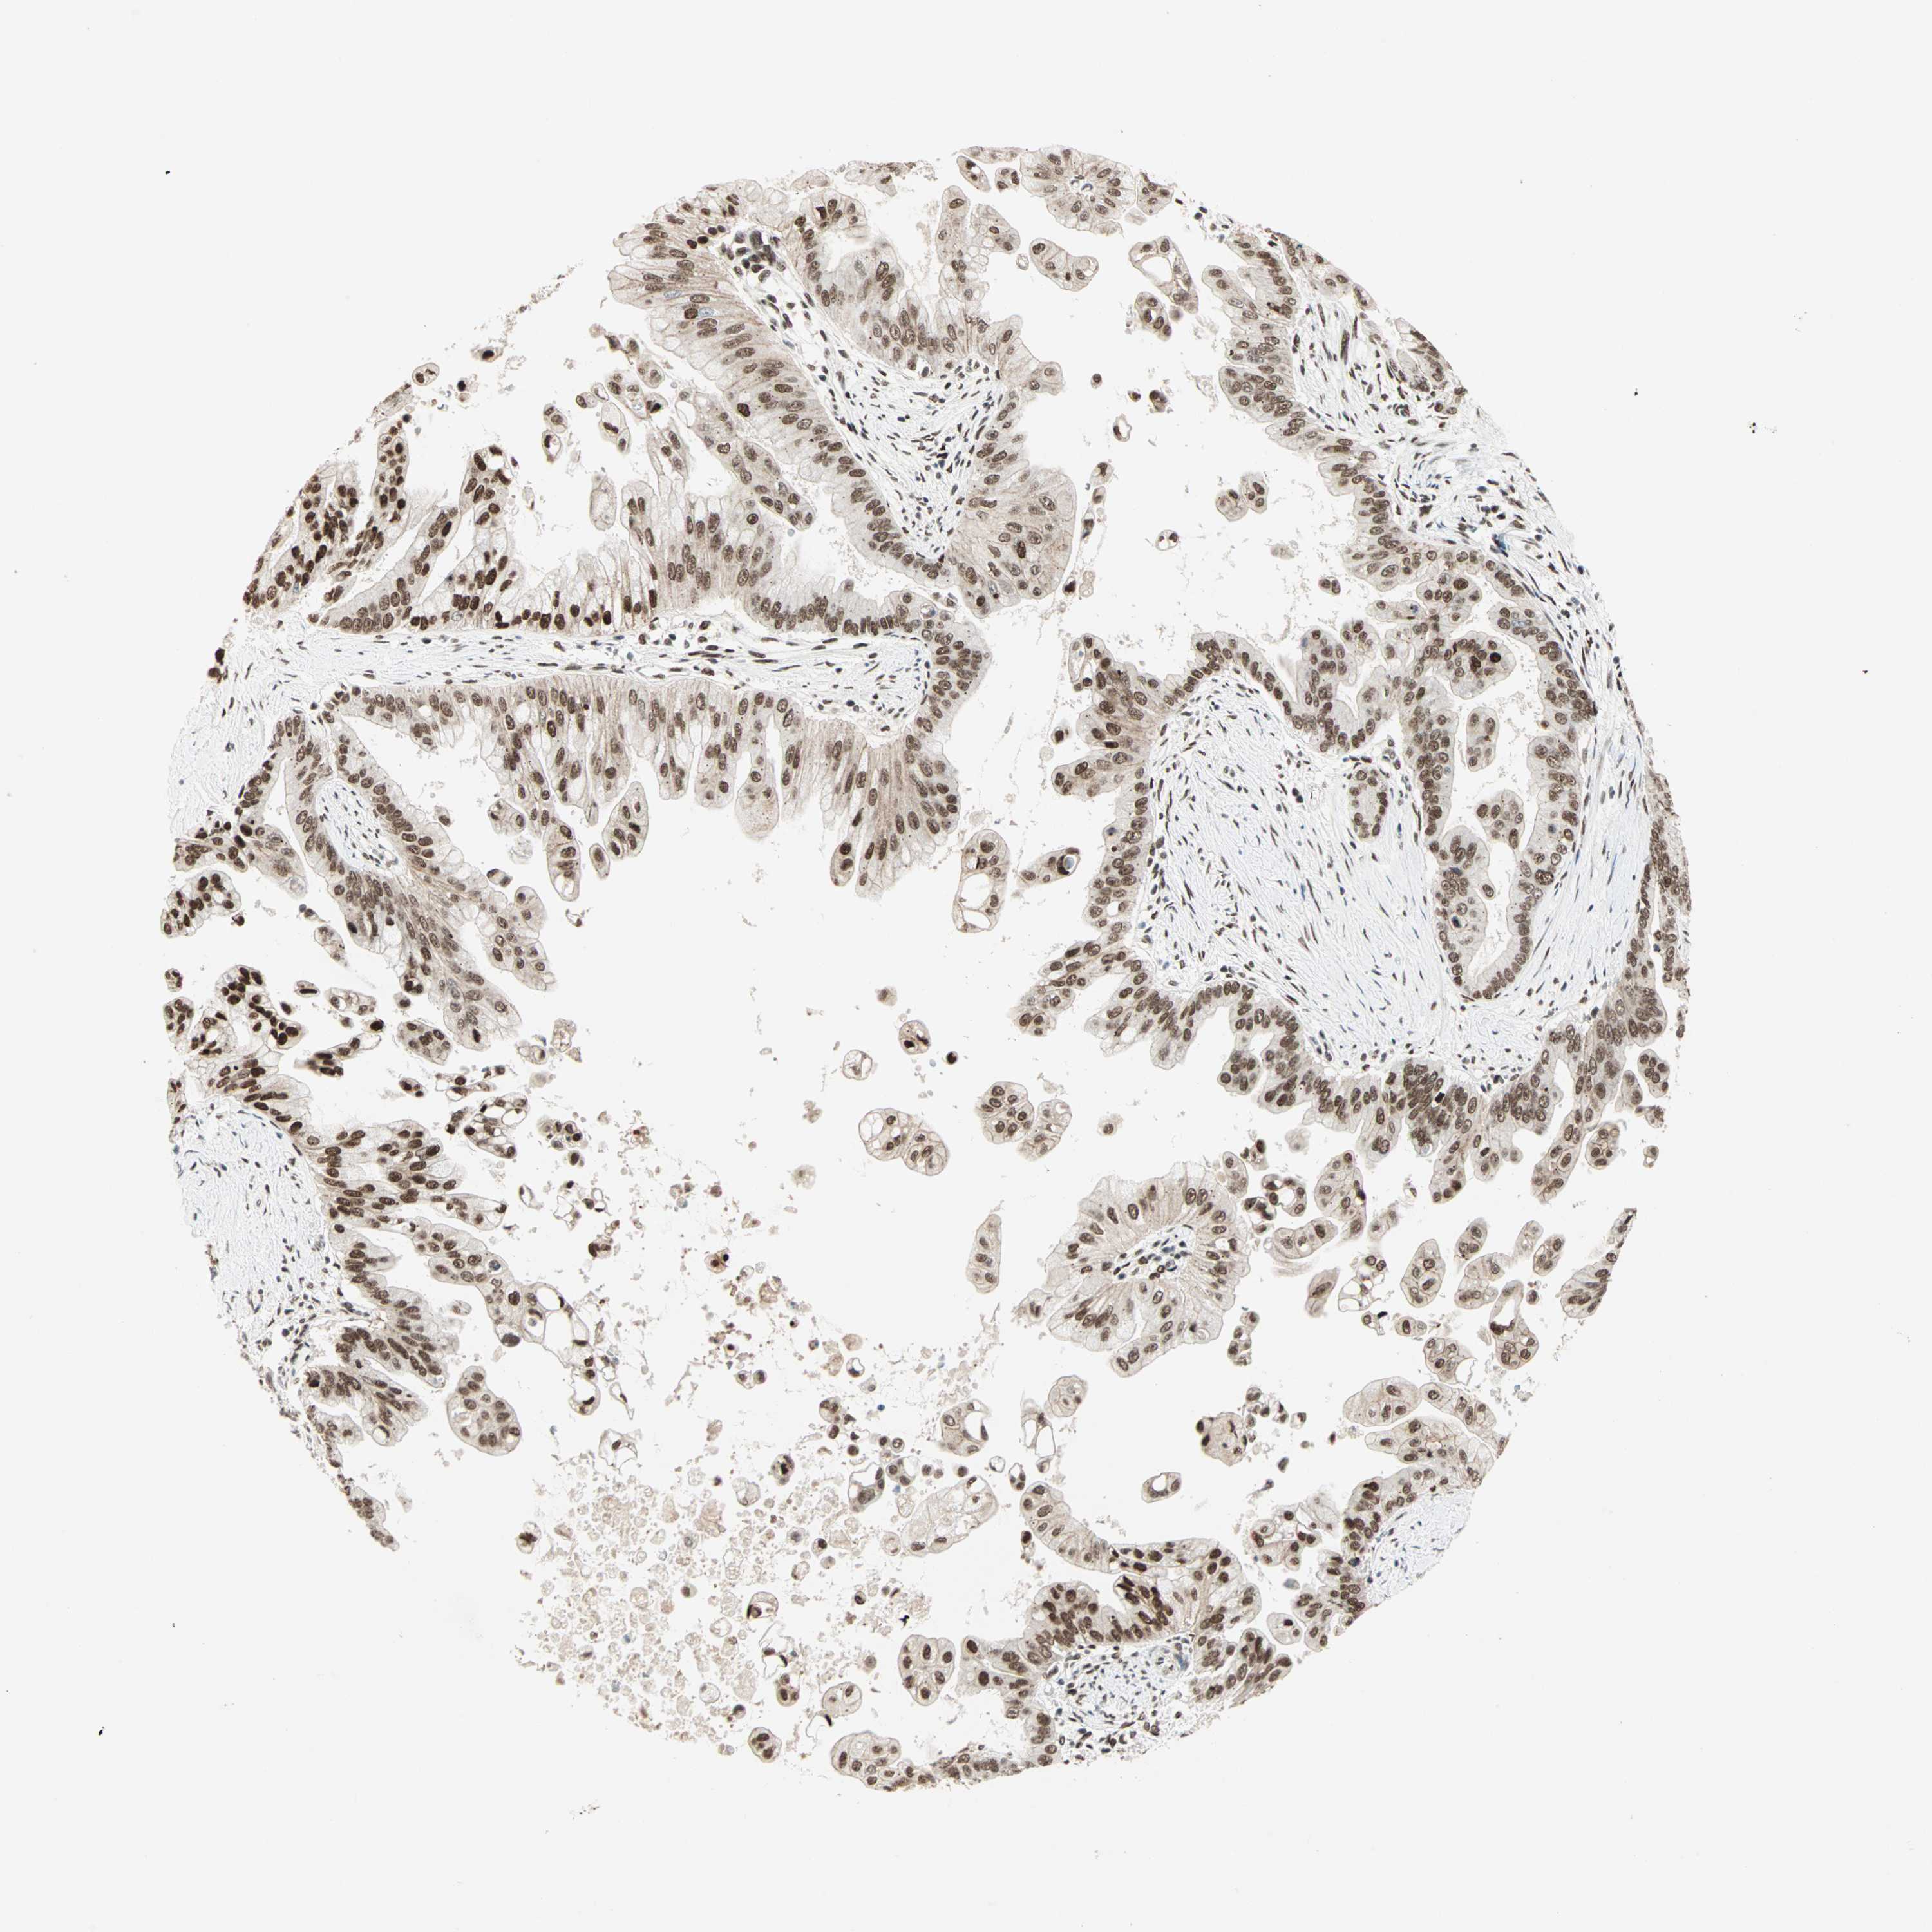

PANCREATIC CANCER - Protein expressioni

A mouse-over function shows sample information and annotation data. Click on an image to view it in a full screen mode. Samples can be filtered based on level of antibody staining by selecting one or several of the following categories: high, medium, low and not detected. The assay and annotation is described here.

Note that samples used for immunohistochemistry by the Human Protein Atlas do not correspond to samples in the TCGA dataset.

Antibody stainingi

Antibody staining in the annotated cell types in the current human tissue is reported as not detected, low, medium, or high, based on conventional immunohistochemistry profiling in selected tissues. This score is based on the combination of the staining intensity and fraction of stained cells.

Each image is clickable and will lead to virtual microscopy that enables deeper exploration of all samples and also displays staining intensity scores, fraction scores and subcellular localization as well as patient and tissue information for each sample.

Antibody HPA005689

Staining

High

Medium

Low

Not detected

Intensity

Strong

Moderate

Weak

Negative

Quantity

>75%

75%-25%

<25%

None

Location

Nuclear

Cytoplasmic/membranous

Cytoplasmic/membranous,nuclear

Adenocarcinoma, NOS

Adenocarcinoma, metastatic, NOS